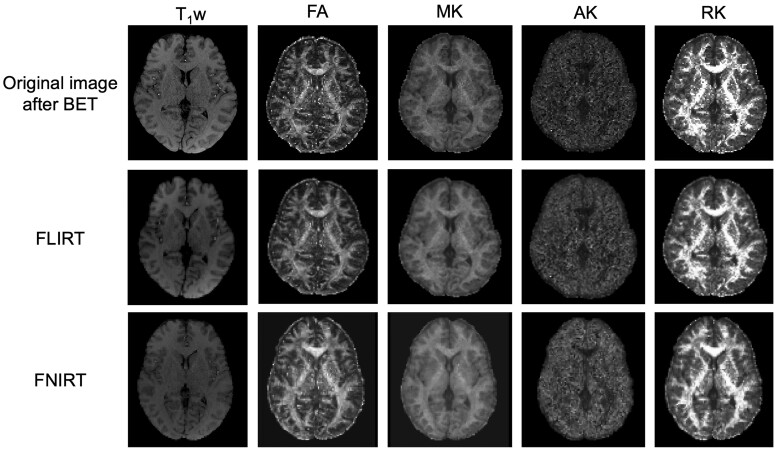

Methods: Thirteen healthy volunteers (mean age, 25.2 years) were examined in this study. On a 3-T MRI system, diffusion dataset for DKI was acquired using an echo-planner imaging sequence, and T1-weghted (T1w) images were acquired. Imaging analysis was performed using Functional MRI of the brain Software Library (FSL). First, registration analysis was performed using the T1w of each subject to MNI152. Second, DTI (eg, fractional anisotropy [FA] and each diffusivity) and DKI (eg, mean kurtosis [MK], radial kurtosis [RK], and axial kurtosis [AK]) datasets were applied to above computed spline coefficients and affine matrices. Each DTI and DKI parameter value for WM areas was compared. Finally, tract-based spatial statistics (TBSS) analysis was performed using each parameter.

Abstract Image